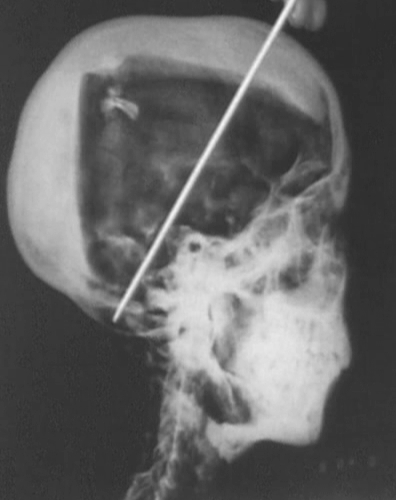

2005년 1월 5일 카이로대학교 소아암학과 Department of Pediatrics Oncology 소속 하니 압델-라만(Hany Abdel-Rahman) 박사 감독 하에 투탕카멘 미라에 대한 CT 촬영이 시작되었습니다.*

엑스레이 검시 때와 마찬가지로 이동식 CT 촬영기가 왕묘 앞에 설치된 후 진행된 이날 검시에서는 총 1천700여 장 CT 영상이 촬영되었고 이후 3월 4~5일 CT 영상 판독 결과를 도출하기 위한 전문가 회의가 소집되었습니다.

그러나 우리의 관심사였던 후두부 가격에 의한 사망설에 대한 증거는 전혀 발견되지 않았습니다.

[각주 1: CT 촬영을 이용한 검시 이전에도 과거에 촬영된 엑스레이 사진을 자세히 검사한 결과 투탕카멘이 살해당했다는 결정적인 증거는 없으나 더 정확한 CT 촬영을 통한 연구가 수행되어야 할 필요성이 절실하다고 평가한 보고서가 발표된 바 있습니다.]